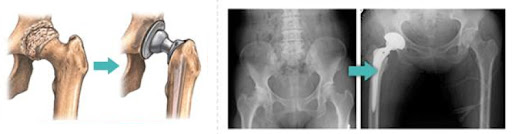

고관절 수술은 다양한 이유로 시행될 수 있지만, 일반적으로는 고관절 관절염, 외상, 또는 선천적인 기형 등으로 인해 통증이나 기능 저하가 나타날 때 이루어집니다. 이 수술에는 인공관절 치환술, 관절경 수술 등의 방법이 있으며, 각각의 수술 방법은 회복 단계와 필요한 시간에 서로 영향을 미칩니다. 고관절 수술의 주된 목적은 통증을 감소시키고, 이동성과 일상생활의 질을 향상시키는 것입니다. 그러므로, 환자는 수술 후 생활 습관을 조절하고, 적극적인 rehabilitative 간호를 통해 빠른 회복을 도모해야 합니다.

- 인공관절 치환술: 가장 일반적인 고관절 수술입니다. 퇴행성 관절염이나 심한 외상으로 인해 고관절이 손상된 경우, 인공 관절로 대체합니다. 이 수술은 대개 1-2시간 가량 소요되며, 회복이 길어질 수 있습니다.